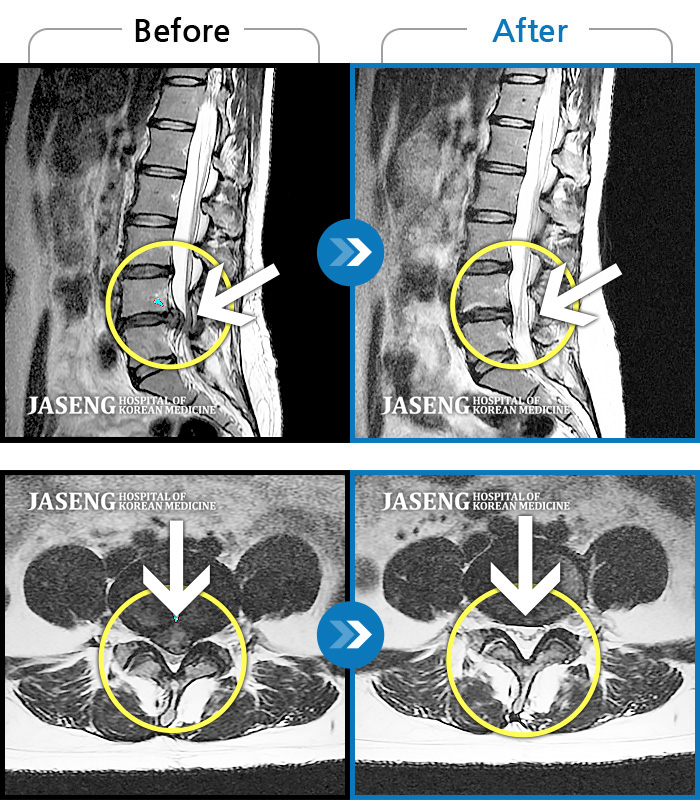

허리디스크

보라매 · 왕오호 원장

좌측 허리 통증 및 좌측 다리 저림

촬영시기

2016.05.21 ~ 2018.04.13

2018.12.28

조회수 692